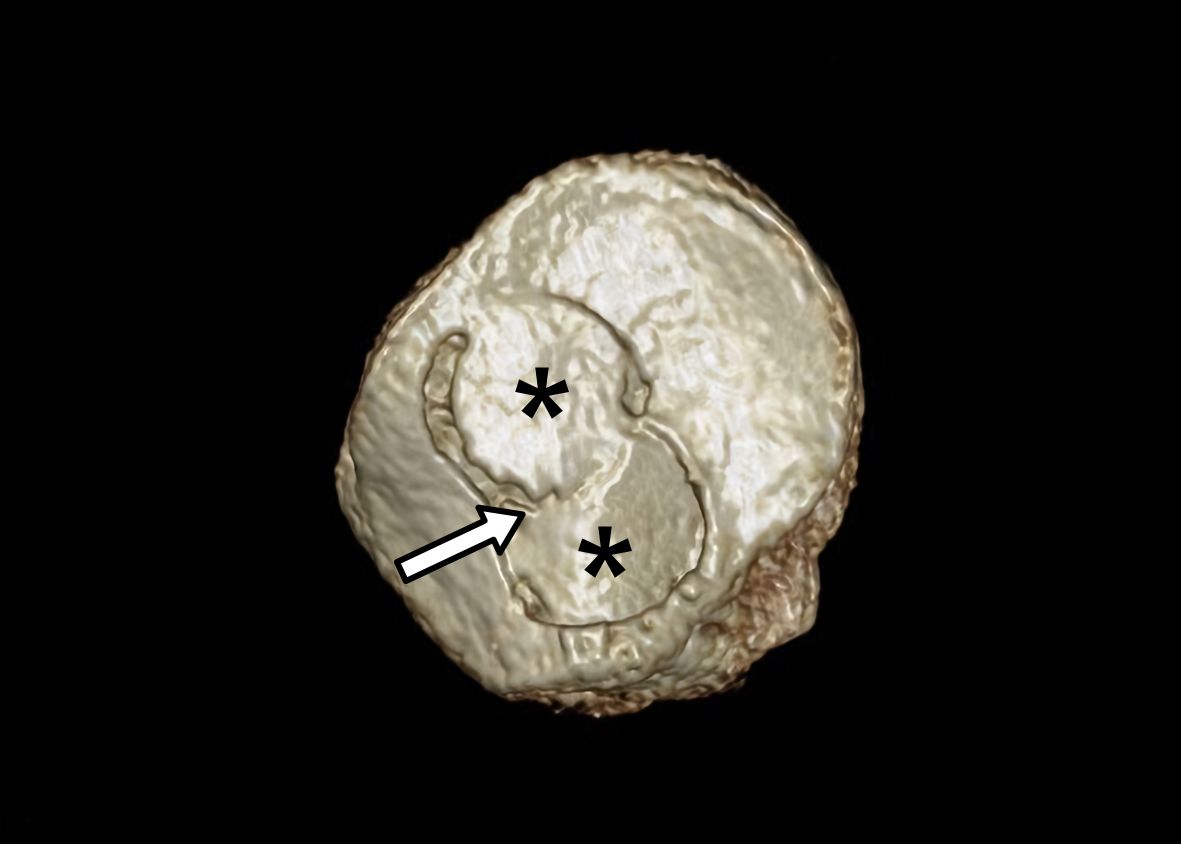

• Shell or Resurfacing technique

is recommended for large or multiple lesions in which a dowel technique is not suitable to cover the entire defect (Figure 4). This technique involves a recipient area and graft preparations that have to be tailored according to the specific location and size of the defect.

Bipolar chondral lesions of the patella and trochlea may be considered a relative contraindication due to the limited success of clinical outcomes and the considerable percentage of failures [37]. This is particularly true when they are compared with isolated Dowell technique transplantation performed in the femoral condyles [38]. The direct relationship between allograft size and graft failure has also been demonstrated for the patellofemoral joint [33]. Then, FOCA procedure in large bipolar patellofemoral injuries have to be done only when an invalidating knee pain makes no other choice reasonable (Figure 4 and 6) [7].